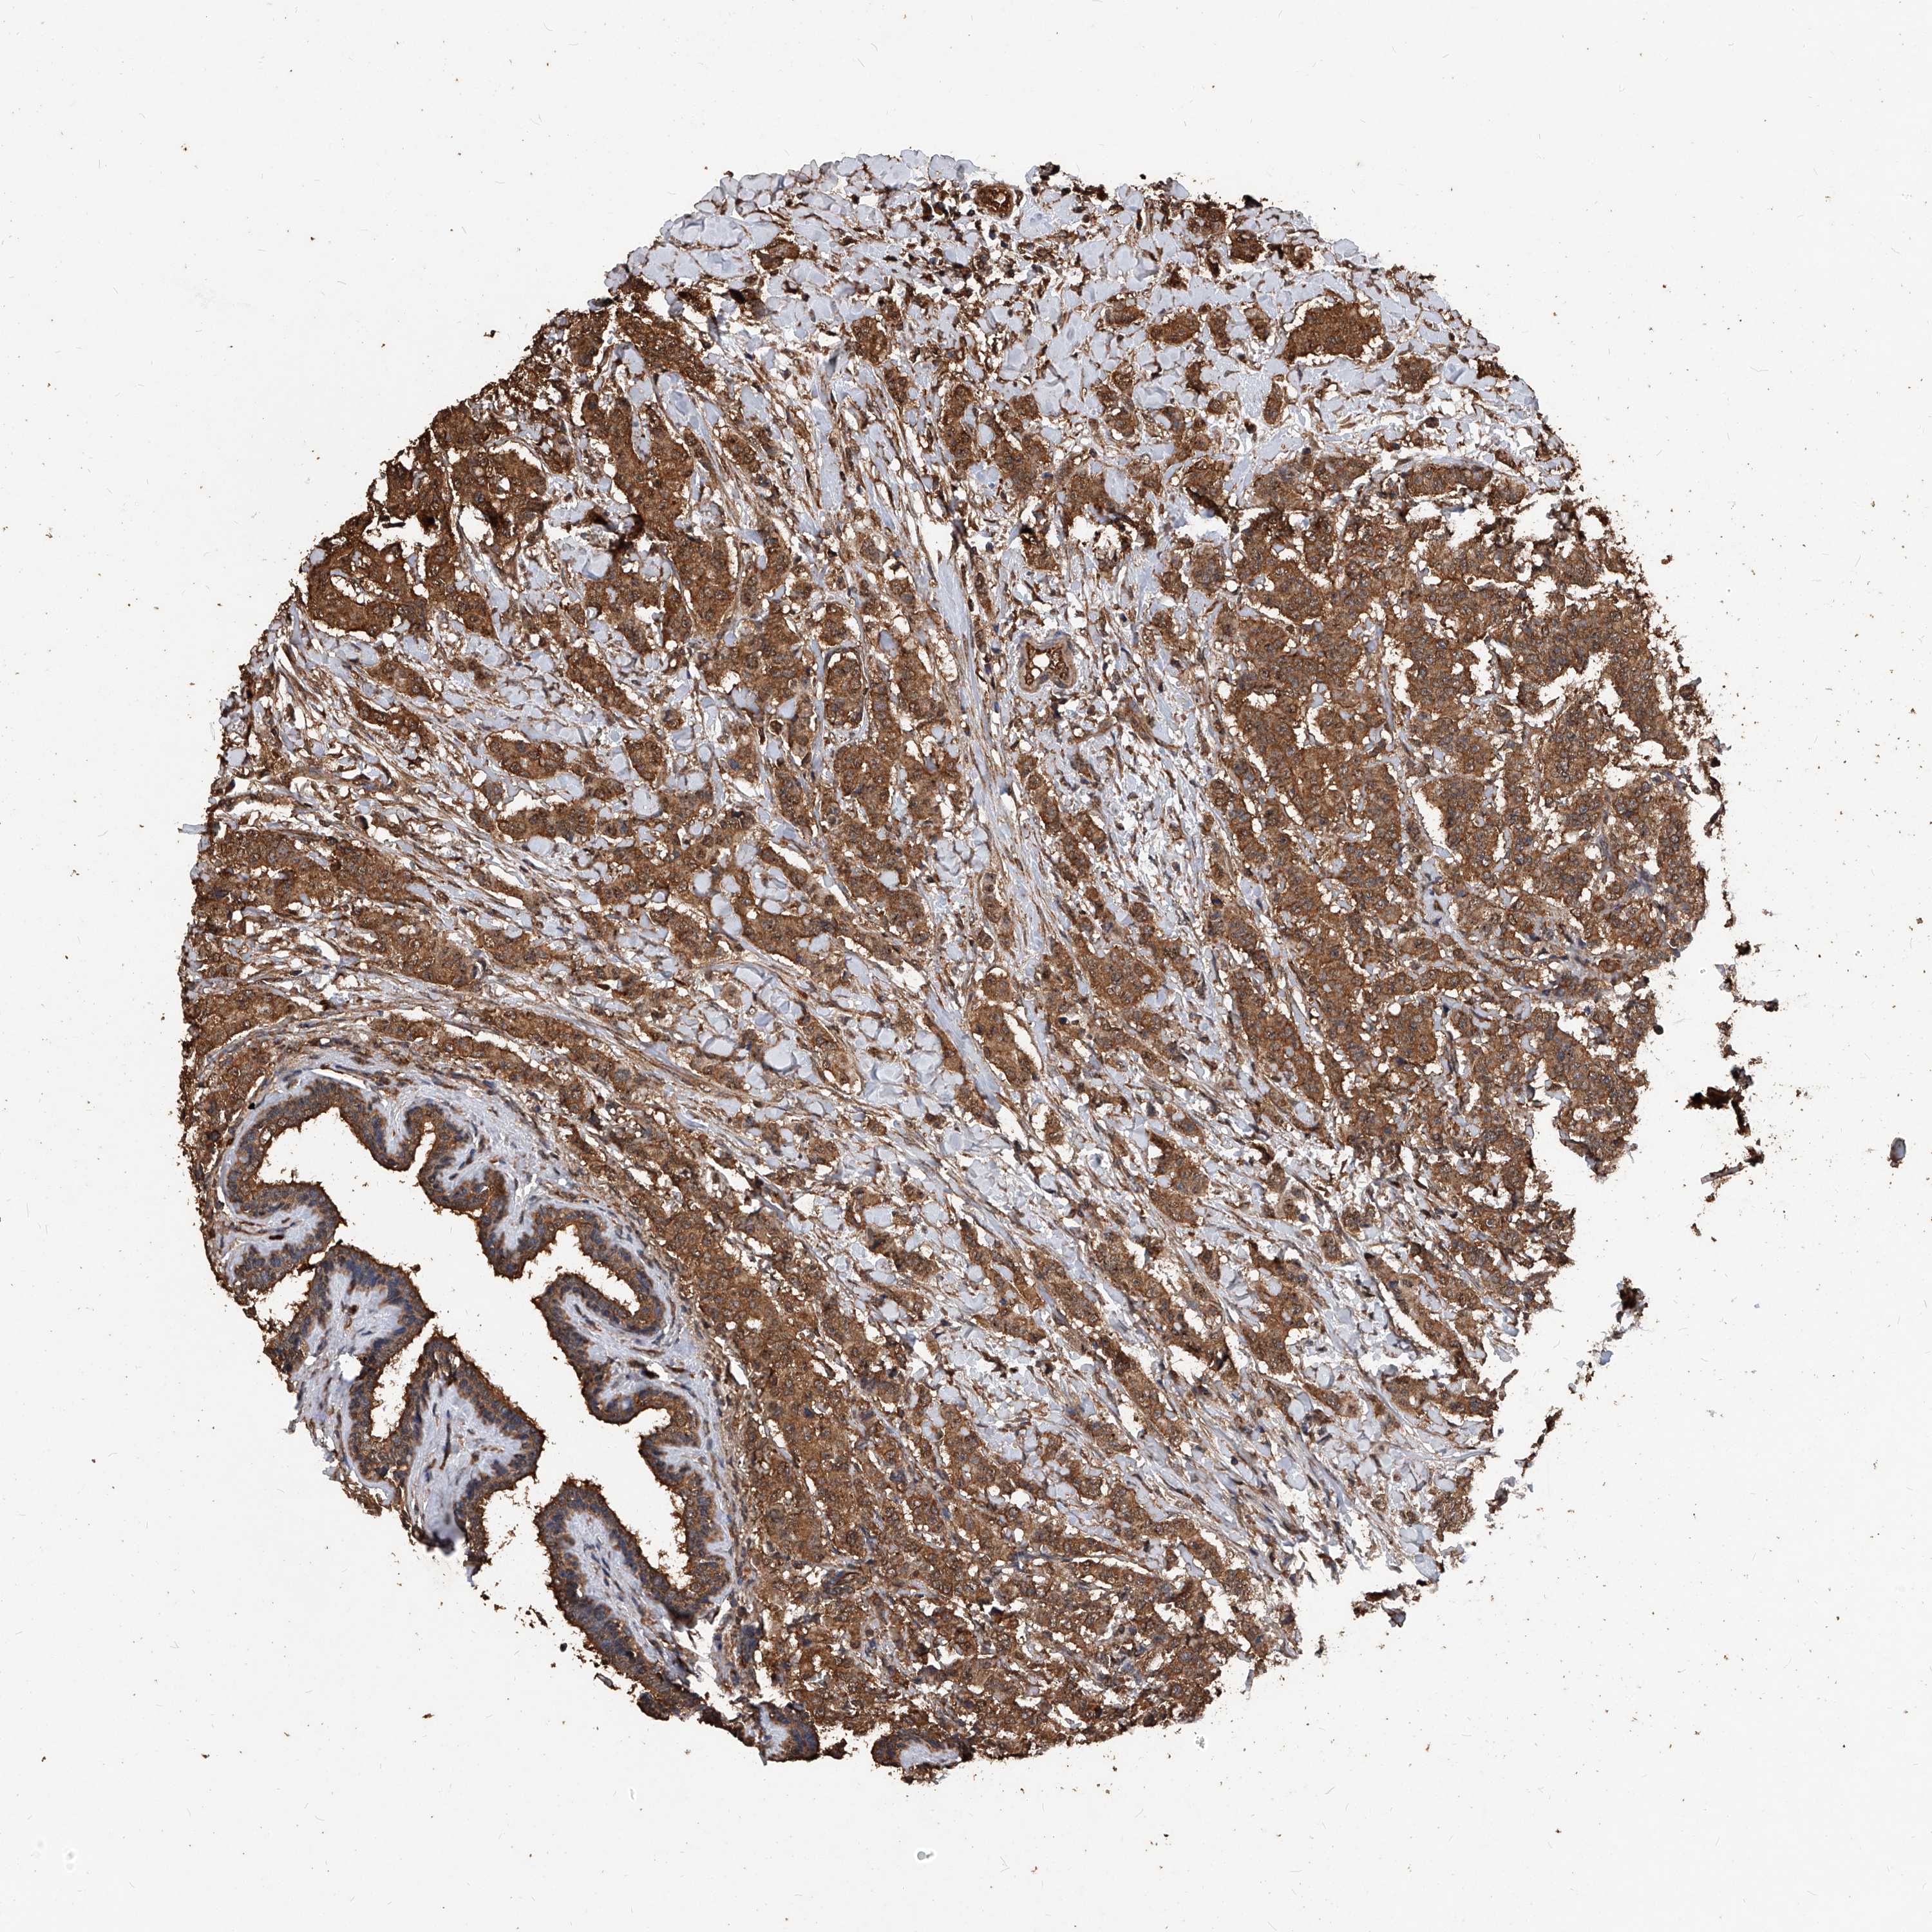

CANCER BREAST CANCER Show tissue menu

BRCA TCGA BRCA VALIDATION PROTEIN EXPRESSION

Breast cancer

Human cancer